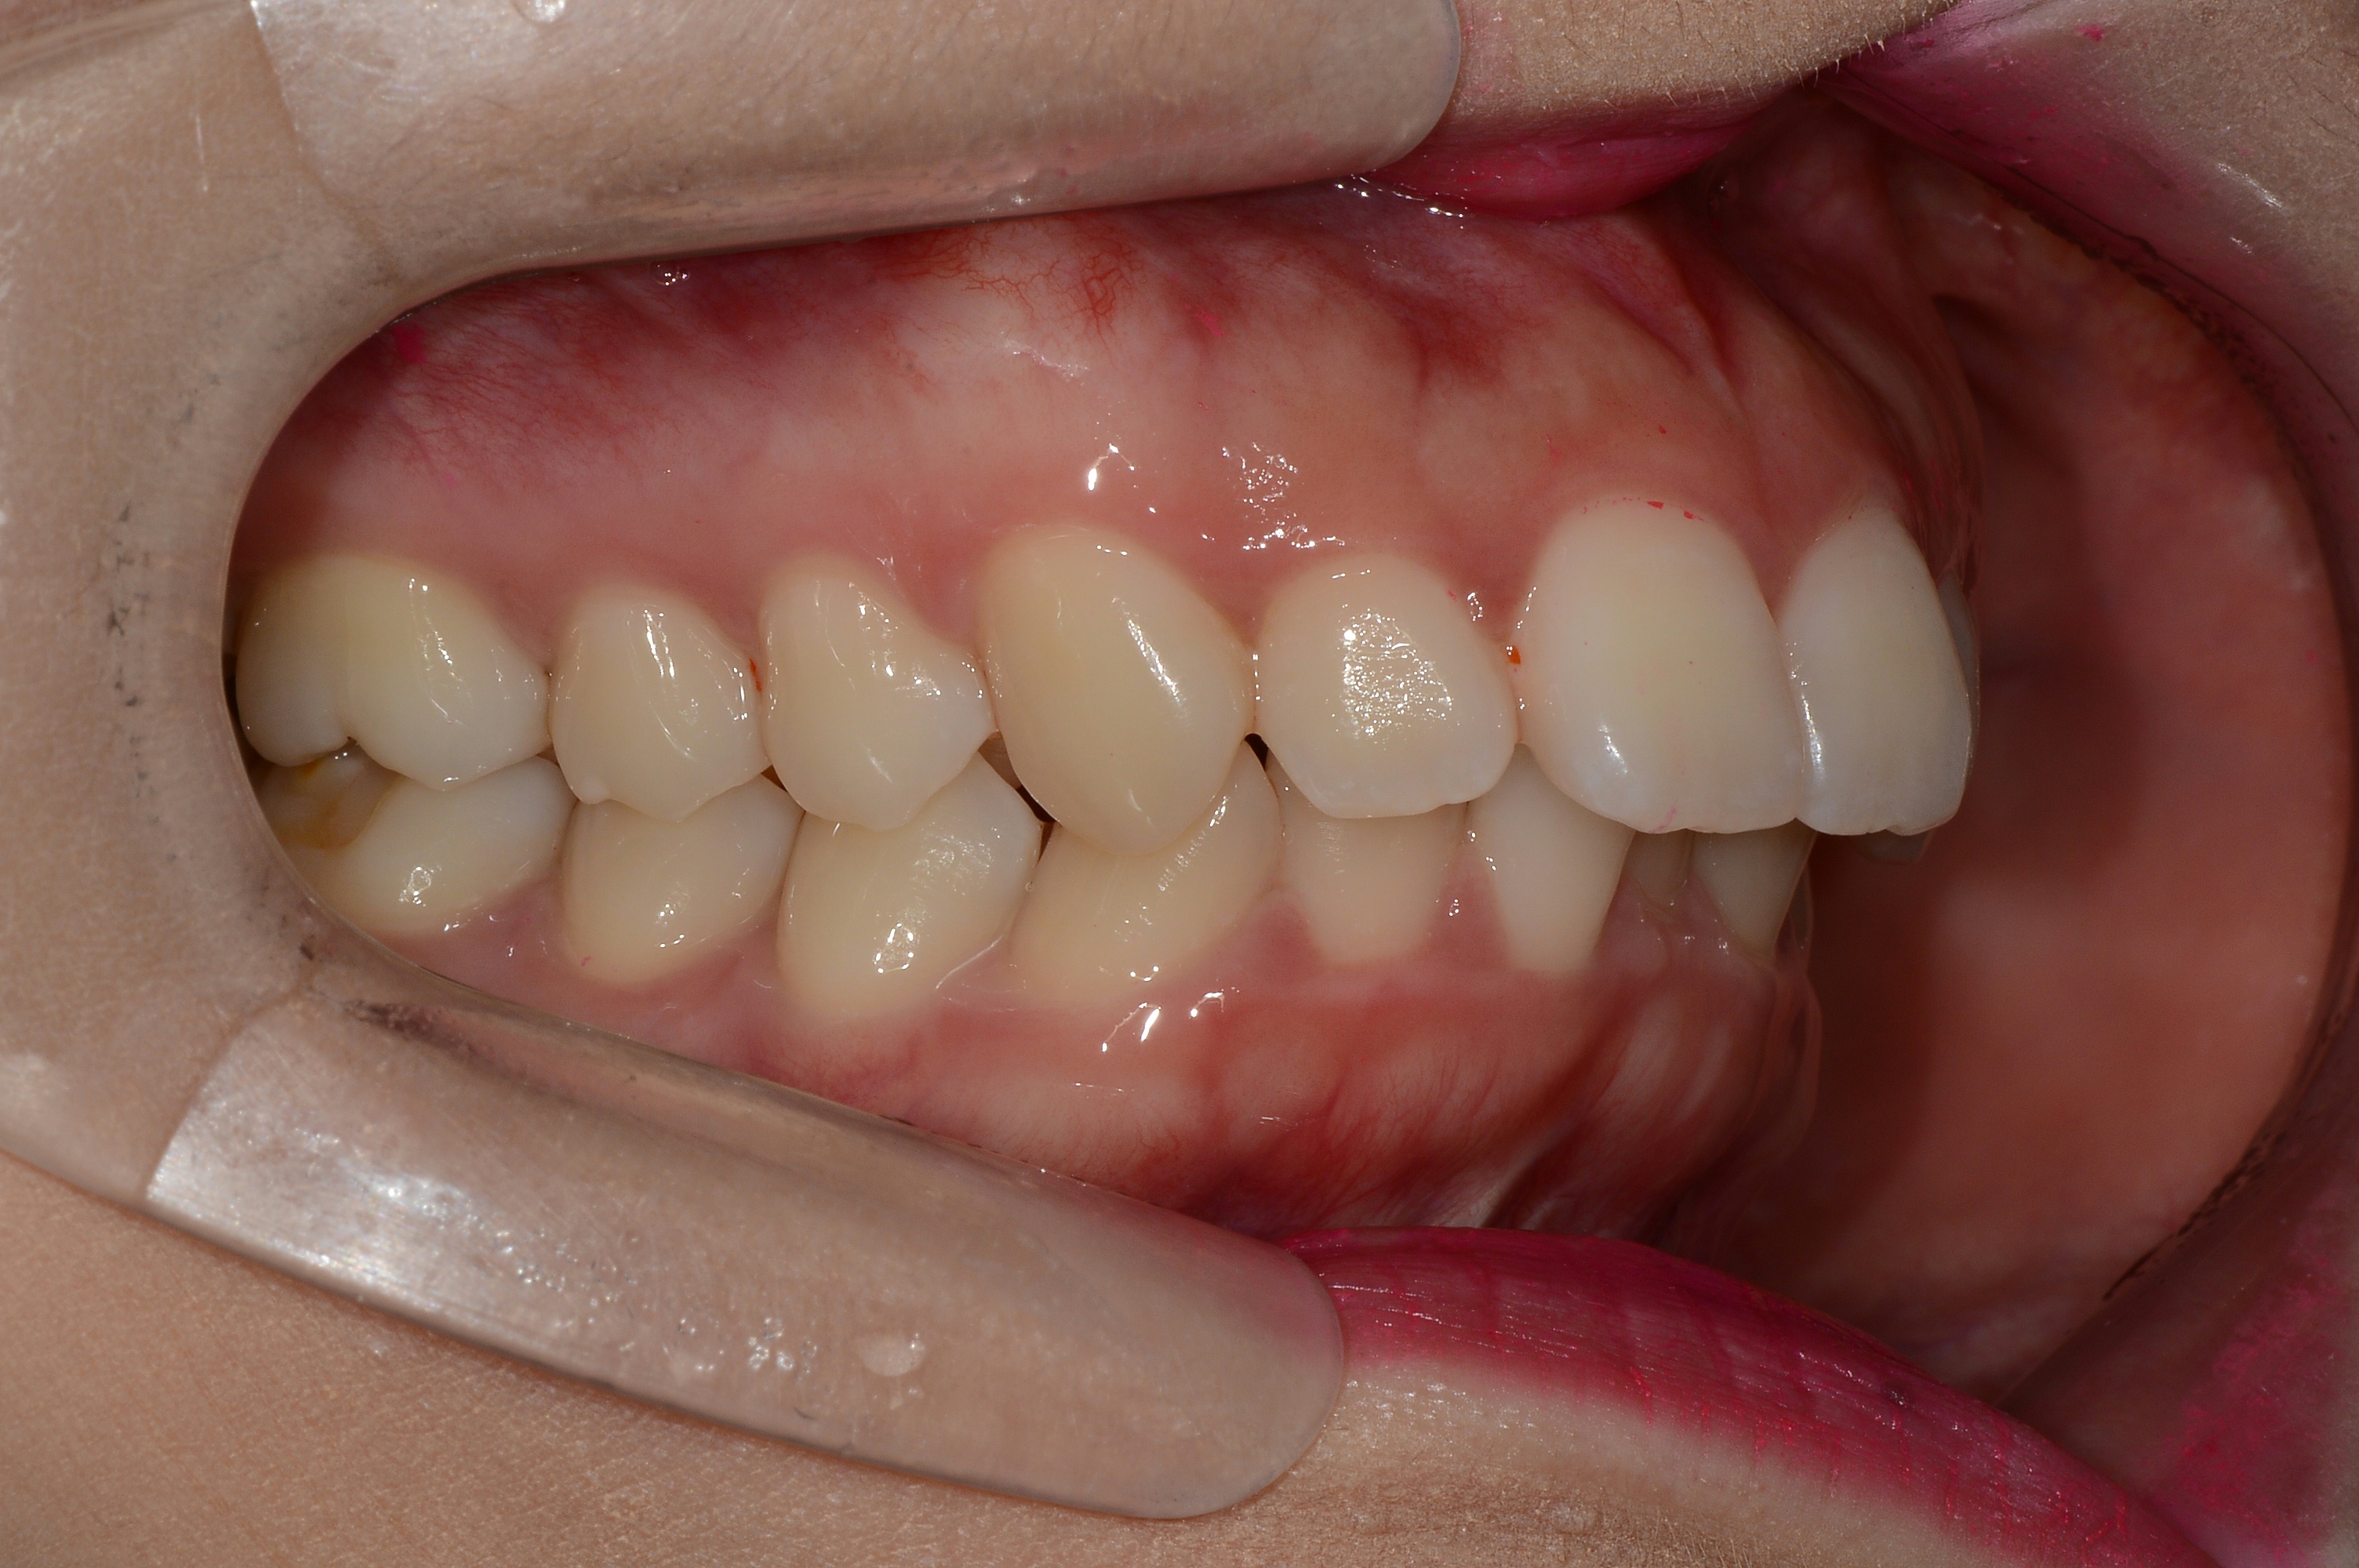

치료 후 사진입니다.